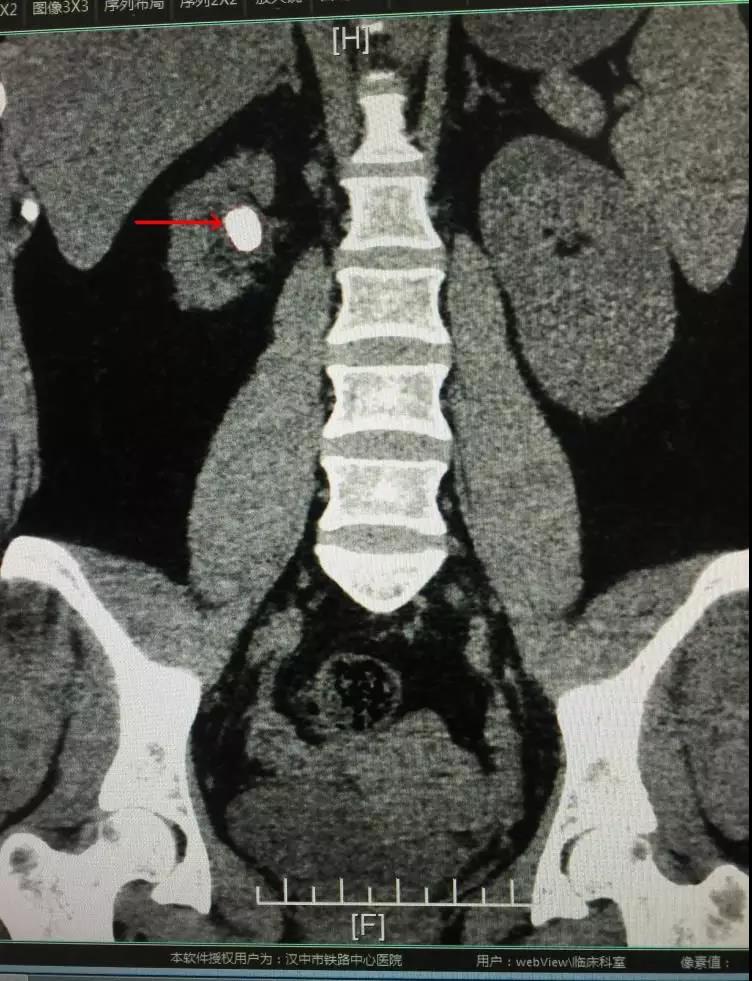

随着生活水平的提高,饮食、生活习惯工作节奏加快,泌尿系结石的患病率逐年增高。大多数不疼不痒的肾结石,容易忽略,以至对肾脏造成功能损害。近期我科收治一位女性患者,3年前发现右肾结石,自认为“又不疼处理它干嘛呢”,直到今年再次体检发现结石增大至约3.0cm,结石长期慢性感染导致右肾严重萎缩,仅有正常肾脏的1/3大,前往省市多家医院就诊结论是切除右侧萎缩肾脏。这无疑对年纪20多岁的她是一个严重打击,“不想切肾”是她心里最真实的声音,通过村上原来患过结石的朋友介绍来到汉中市铁路中心医院就诊。

入院后科主任舒翼充分的评估病情,考虑患者右肾虽然萎缩,但仍有部分功能,决定行经皮肾镜钬激光碎石术(PCNL术)处理结石,保留肾脏。因患者体型肥胖,加之右肾萎缩,为手术中的穿刺增加了难度。最终仍克服困难,手术顺利完成。赢得了患者全家及所在村庄的一片赞赏。